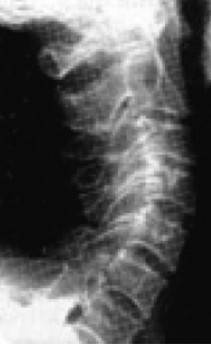

Причем, опять же, рост этого горбика она объясняет исключительно «солями» – остеохондрозом – и не связывает с изменившейся статикой своего позвоночника. В норме позвоночник, как известно, не должен быть прямым, как палка, а иметь физиологические изгибы. В частности, шейный отдел, состоящий из 7 позвонков, в норме должен быть чуть прогнутым внутрь (рис. 13).

Иллюстрация к книге — Биогимнастика для лица: система фейсмионика [i_017.jpg]

Рис. 13. Нормальная статика шейного отдела